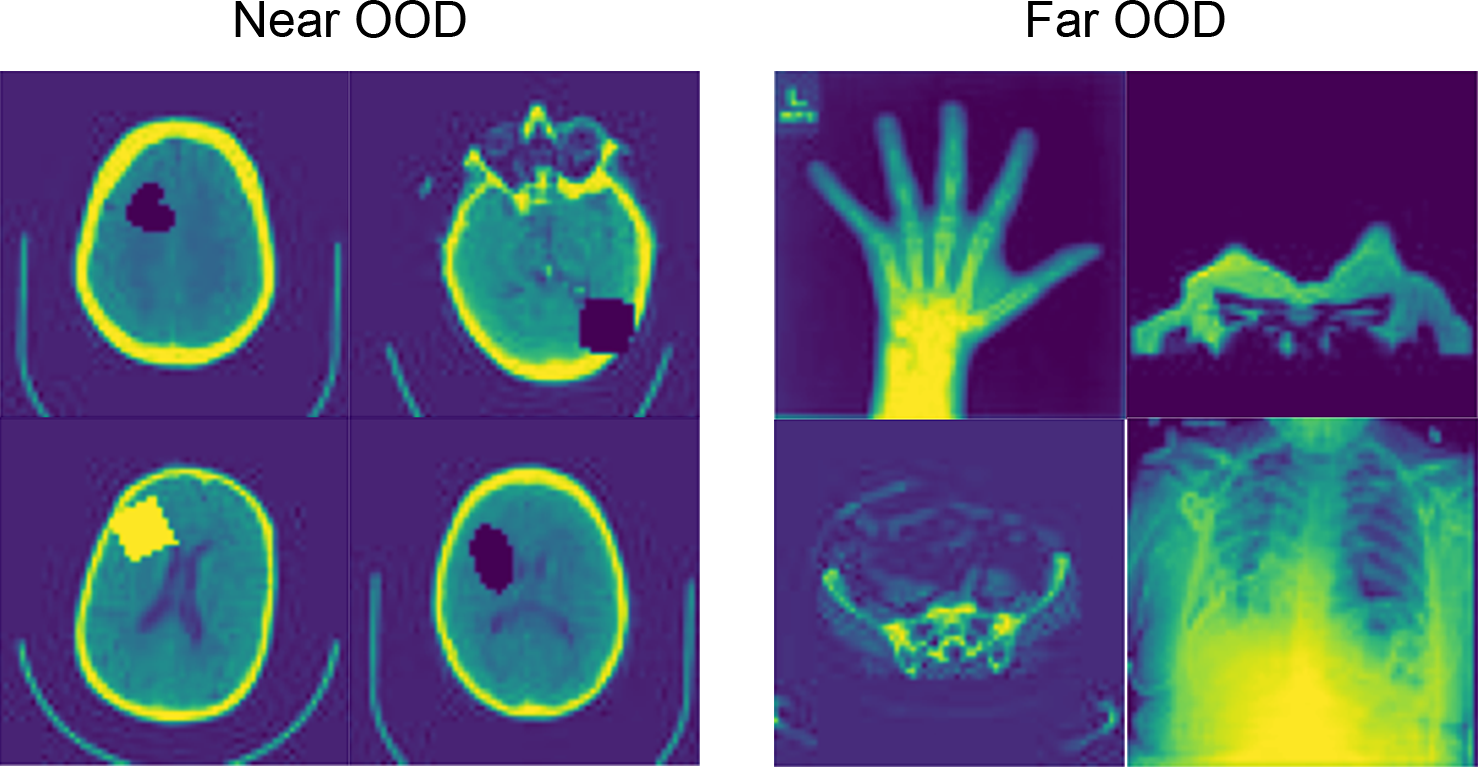

4.2 Experiment #2 – Image-wise Anomaly Detection on Synthetic Data

Next, we evaluated our method to detect anomalous (out-of-distribution - OOD) images, again on a synthetic setting. Using the same models trained from Experiment #1, we obtained the mean log-likelihood for each image. We used 1,000 images from the HeadCT class as the in-distribution test set, the 100 HeadCT images contaminated by sprite anomalies as the near OOD set, and 1.000 images of each other MedNIST classes as the far OOD set (see the appendix for details). We use the area under the receiver operating characteristic curve (AUROC) as performance metric, with in-distribution test set and out-of-distribution being the labels. This way, we have a threshold-independent evaluation metric. We also measure the area under the precision recall curve (AUCPRC), where it provides a meaningful measure for detection performance in the presence of heavy class-imbalance. Finally, we also computed the false positive rate of anomalous examples when the true positive rate of in-distribution examples is at 95% (FPR95), 99% (FPR99) and 99.9% (FPR999).

tab:syntdet shows that our transformer-based method achieved an AUCROC of 0.921 and 1.000 for near OOD and far OOD, respectively. This is a improvement compared to a method based on the error of reconstruction obtained from a VAE model. We also evaluated our method with a VQ-VAE trained to reconstruct all the categories from the MedNIST dataset (“general purpose VQ-VAE”) and the ensemble of transformers trained on HeadCT images only. In this configuration, we try to mitigate the influence of the encoder in the anomaly detection. This approach would reduce the ability of the encoder to map an OOD image to a familiar in-distribution latent representation, which could possibly affect the transformer performance. This new configuration achieves a slight better performance (AUCROC=0.932 for near OOD and AUCROC=1.000 for far OOD).

In this experiment, we used the same training set from the Experiment #1. For evaluation, we used 1,000 images from the HeadCT class as the in-distribution test set, the 100 HeadCT images contaminated by sprites anomalies as the near out-of-distribution set (near OOD), and 1,000 images of each other classes from the MedNIST dataset (AbdomenCT, BreastMRI, CXR, ChestCT, and Hand) as the far out-of-distribution set (far OOD) (Figure LABEL:fig:S4). To train our general purpose VQ-VAE, we added 8,000 images from each other classes to our training set and 1,000 images to our validation set.

fig:S4